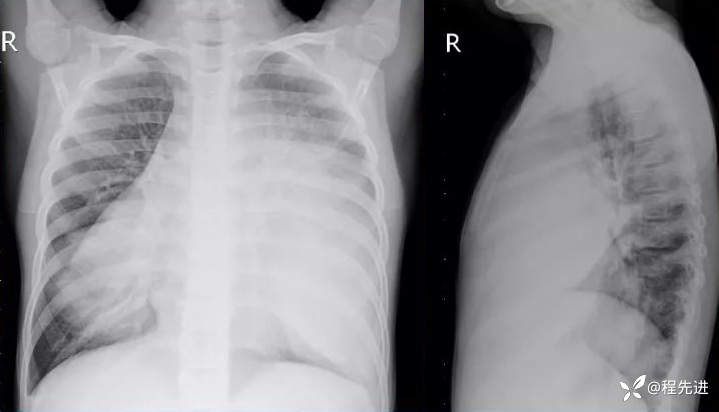

胸片